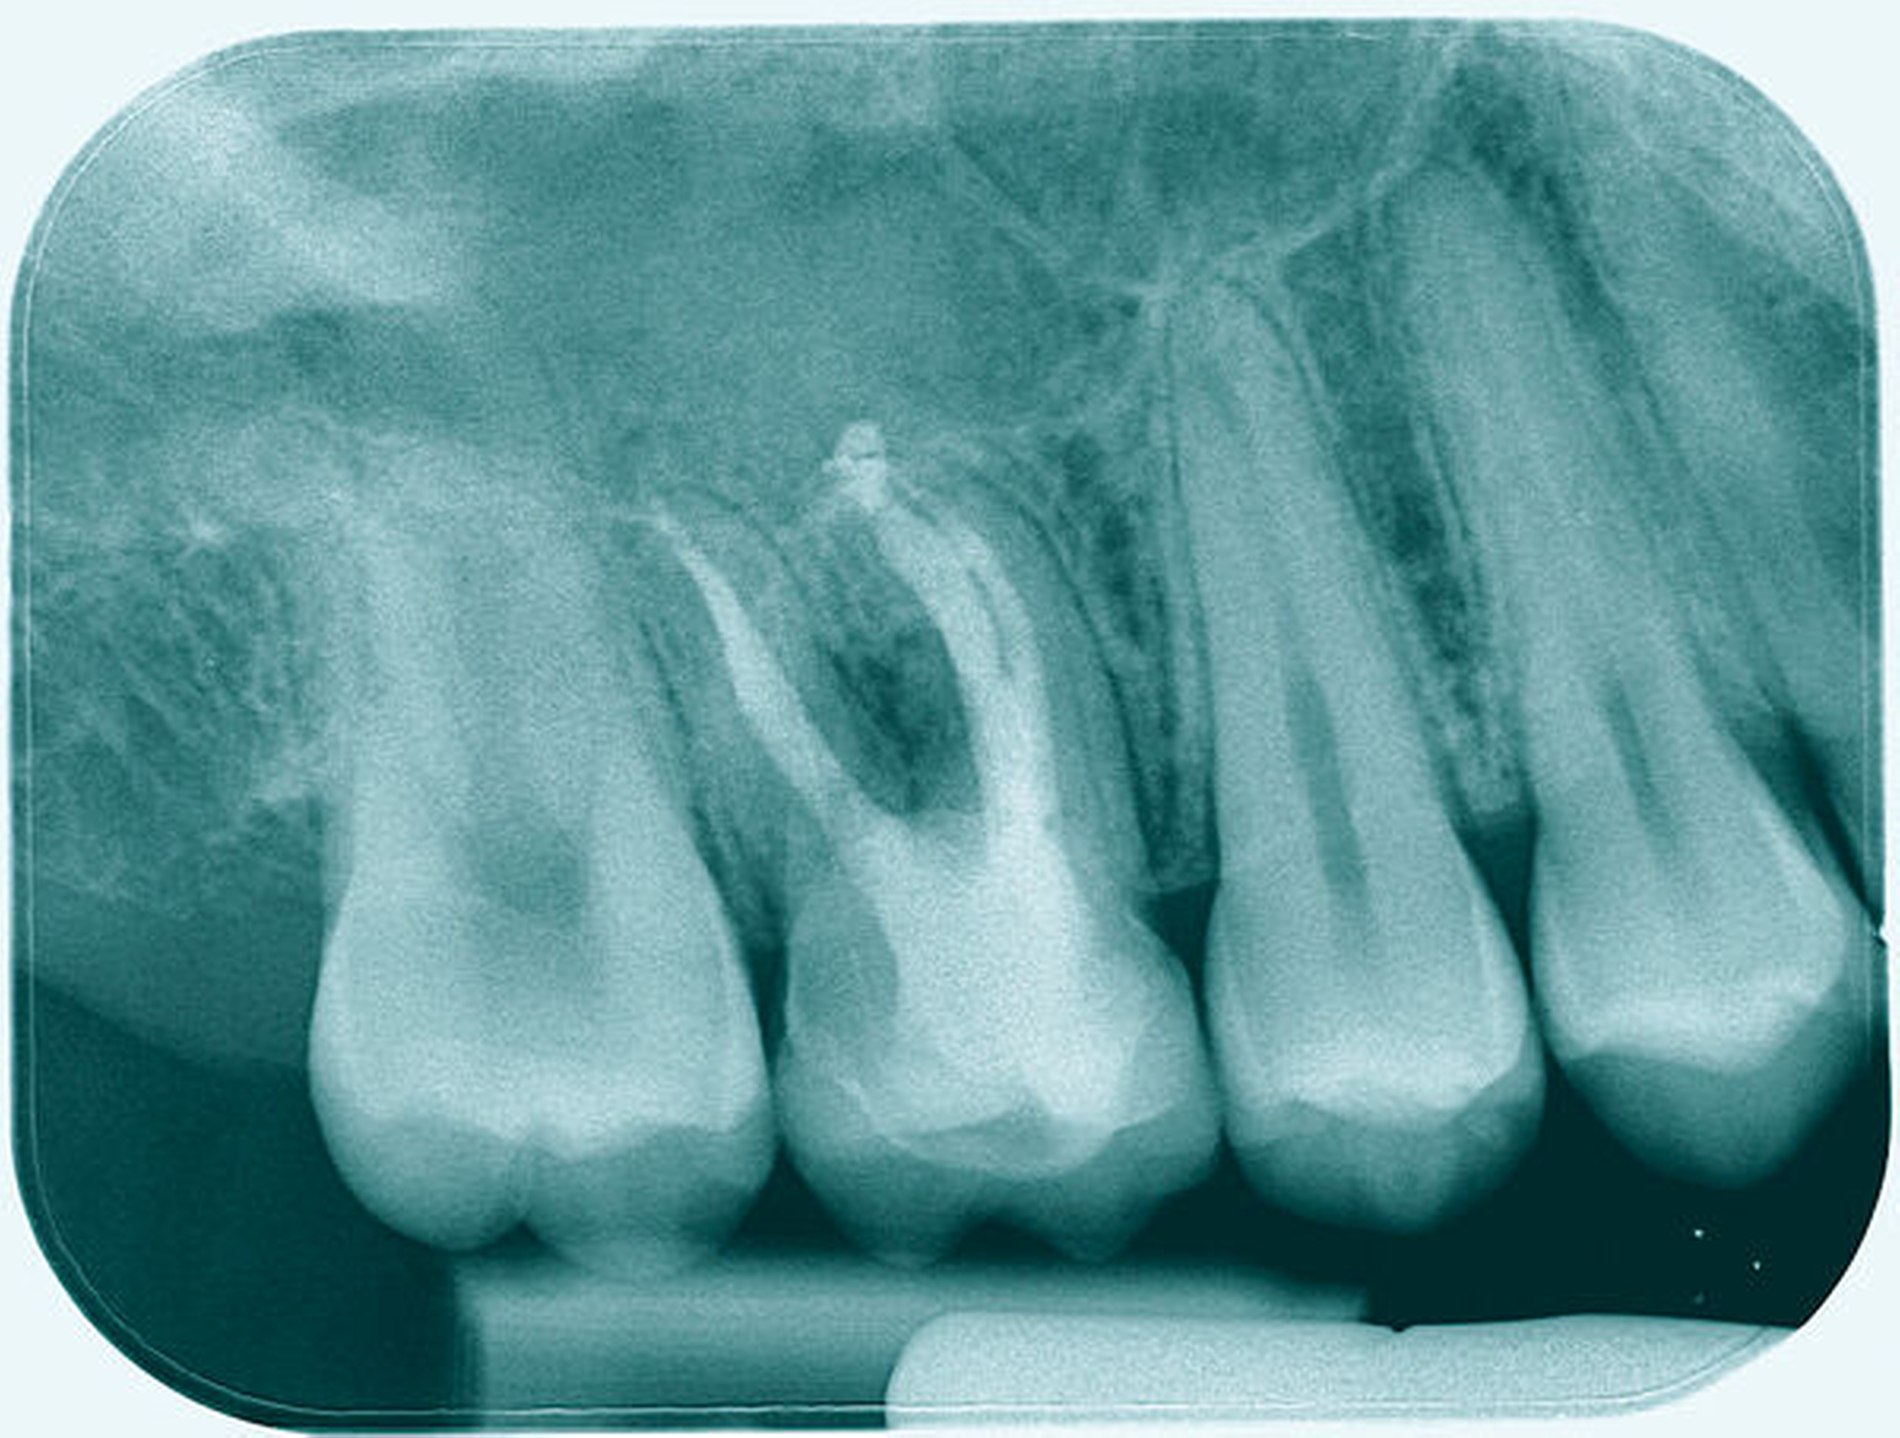

Eine 53-jährige Patientin stellte sich 2015 mit plötzlich aufgetretenen, starken Beschwerden an Zahn 16 und der Bitte um Abklärung vor. Es erfolgte die klinische und röntgenologische Befundung des Zahnes, der neben einer apikalen Parodontitis auch eine große, fast bis in die Furkation reichende Kronenrandkaries an der mesiobukkalen Wurzel aufwies. Um diesen vorhersagbar versorgen zu können, wurde der Patientin die endodontische Behandlung mit Amputation der mesiobukkalen Wurzel und anschließender Versorgung mittels Vollkrone als Alternative zur Extraktion aufgezeigt. Sie entschied sich für den Zahnerhalt.

So folgte nach der Wurzelfüllung die Amputation der mesiobukkalen Wurzel. Der Zahn wurde nach der Amputation auf Wunsch der Patientin zunächst mit einem Langzeitprovisorium versorgt, das im Verlauf gegen eine definitive Versorgung ausgewechselt wurde. Die Patientin ist seitdem an 16 beschwerdefrei, der Zahn ist stabil und hat eine gute Langzeitprognose.